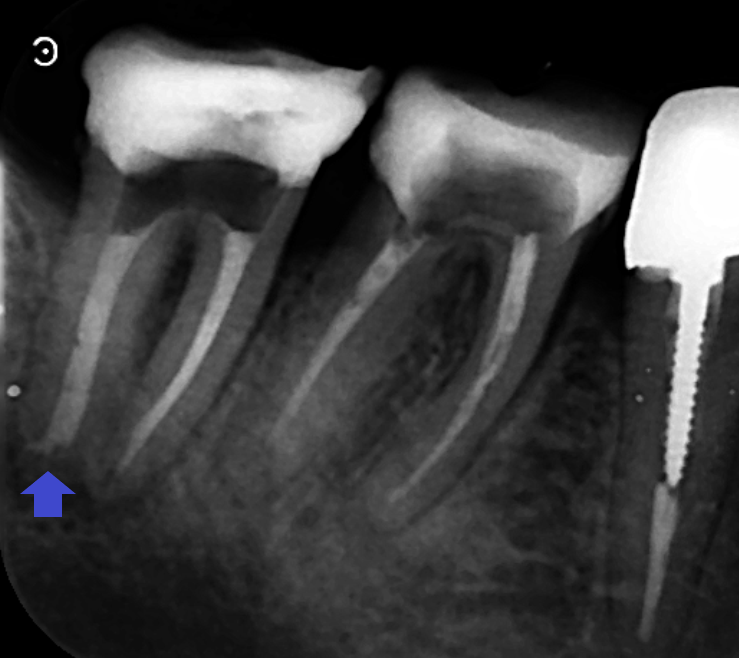

精密再根管治療を行いました。画像は、根管充填時のレントゲン写真です。遠心根の根の先の90°近く曲がった根管の先まで根管充填できています。